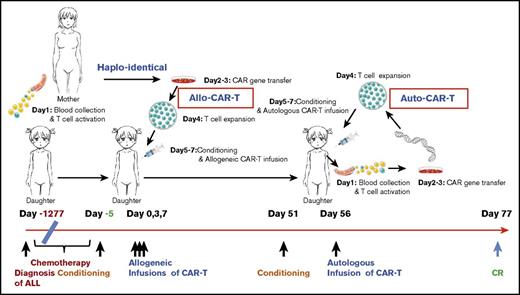

By March 2015, all chemotherapies failed, and she developed pancytopenia with 27% leukemic blasts in the BM with hypocellularity. This was complicated by pulmonary infections and gastrointestinal bleeding, and her condition deteriorated because of disease progression. In the absence of autologous T cells, haploidentical allogeneic CAR-T strategy was considered (Figure 1).

The time line and key events of the allogeneic/autologous CAR-T treatment regimen. The patient was diagnosed with ALL on day −1277 (−42.5 months) and received extensive chemotherapy but developed refractory relapses with lung infections. Maternal source CD19 CAR-T cells were prepared based on a 5- to 7-day CAR-T–cell preparation protocol as illustrated on the top. Allo–CAR-T cells were infused on days 0, 3, and 7, after conditioning chemotherapy. The patient achieved a partial response (PR) in 50 days and received an auto–CAR-T infusion on day 56 after conditioning chemotherapy. CR was achieved on day 77.

The time line and key events of the allogeneic/autologous CAR-T treatment regimen. The patient was diagnosed with ALL on day −1277 (−42.5 months) and received extensive chemotherapy but developed refractory relapses with lung infections. Maternal source CD19 CAR-T cells were prepared based on a 5- to 7-day CAR-T–cell preparation protocol as illustrated on the top. Allo–CAR-T cells were infused on days 0, 3, and 7, after conditioning chemotherapy. The patient achieved a partial response (PR) in 50 days and received an auto–CAR-T infusion on day 56 after conditioning chemotherapy. CR was achieved on day 77.

The patient received cyclophosphamide 400 mg/m2 and fludarabine 30 mg/m2 conditioning regimen on day −5 to −3 prior to CAR-T infusion. Allogeneic CAR-T cells from her mother were infused at 0.54 × 106, 0.5 × 106, and 0.9 × 106 per kg of patient’s body weight on days 0, 3, and 7, respectively. The patient developed fever at 38.5°C with scattered maculopapular rashes and pruritus on her back and neck on day 1. Based on prior CAR-T experiences,7-9 she was given 12.5 mg etanercept (anti-TNF-α antibody), and the patient defervesced. Her temperature fluctuated over several days with new onset of facial rashes, and repetitive doses of etanercept were given to control fever (Figure 2A).

The CBC recovery was accompanied by disappearance of allo–CAR-T cells and increased MRD. Therefore, a second CAR-T course from her own source was initiated. At time of apheresis, the collected cells were 100% of her own based on genotyping, with an absolute lymphocyte count of 0.97 × 109/L and 45% CD3 T cells. Cyclophosphamide 400 mg/m2 and fludarabine 30 mg/m2 conditioning regimen was given on day 51, and autologous CAR-T cells (0.16 x 106/kg) were infused on day 56, which was well tolerated. CAR-T–cell expansion was detected on day 64, and the patient received etanercept for an associated fever. Her temperature returned to normal by day 66. On day 78, 23 days after the auto–CAR-T infusion, BM examination indicated CR by histology and flow cytometry (Figure 2D). Chromosomal analysis showed complete normal phenotype (46, XX) without abnormal clones. Computed tomography (CT) scans of lungs revealed complete resolution from previous infections by day 83 (Figure 3). Because of the lack of matched unrelated donor, and a negative test result for donor specific antibody, the patient subsequently underwent haploidentical hematopoietic stem cell transplantation from the same donor 2 months after the auto–CAR-T infusion.